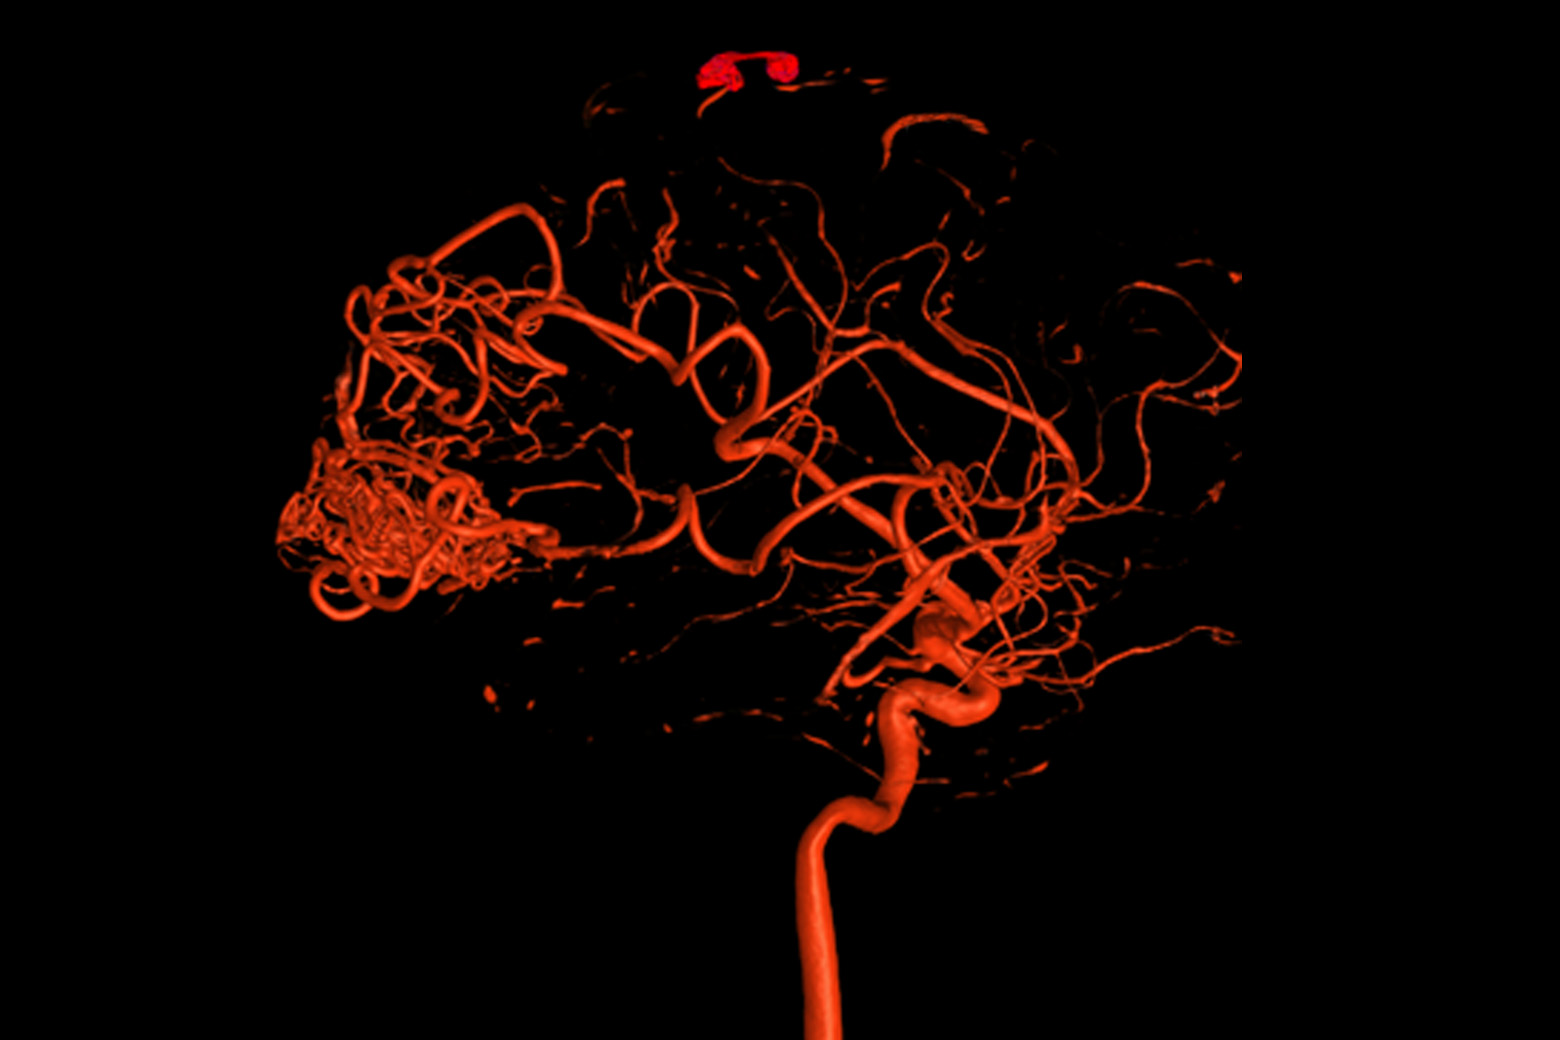

- Functional MRI with diffusion tractography mapped adjacent eloquent brain surfaces and white matter anatomy.

Functional MRI (fMRI) with diffusion tractography, conducted by neuroradiologist Timothy M. Shepherd, MD, PhD, confirmed that the AVM did not involve eloquent cortical regions and provided detailed mapping of the patient’s white matter anatomy (Slide 2).

“Dr. Riina and I determine eloquence based on direct fMRI visualization of patient tasks,” Dr. Shepherd says. “We also look at additional important cortical regions, like frontal eye fields and the supplementary motor area. We then map the white matter anatomy that connects all these regions.” This advanced imaging provides a more complete picture for safer treatment planning, Dr. Shepherd says.